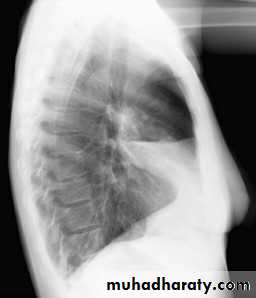

Normal chest XR PA & lateral view

Look carefully on both diaphragmatic cruse costo & cardio phrenic angles

6.lateral film position

8.normal chest XR PA & lat. view

9.normal radiologic anatomy of the chest

10.normal chest anatomy